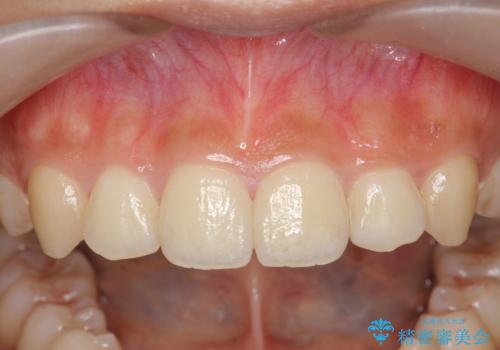

- 前歯のガタつき、上下たがい違いになっている歯並び(クロスバイト)の改善を求めて来院されました。

インビザラインによる矯正治療を行いますが、クロスバイトの改善をワイヤー部分矯正で事前に行うことにより治療期間の短縮する治療計画を立案します。

上下すれ違った噛み合わせはマウスピースでは改善に時間がかかり、またねじれが残ってしまうことも多々見られます。

マウスピース矯正を行う前に、これらの症状の改善の得意なワイヤー部分矯正を行うことで治療期間を短縮し、確実にすれ違いを改善することができます。